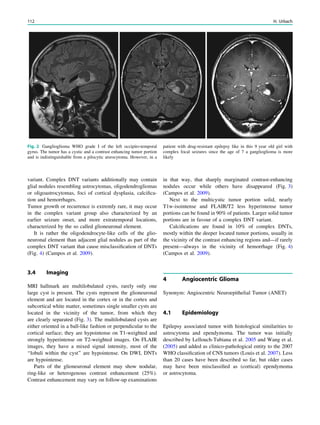

Fig. 1 Digital photogram of the brain surface before placement of a

subdural 8 9 8 grid. A second photogram was taken after grid

placement and digitally replaced by a schematic drawing detailing the

results of electrical stimulations and ictal/ intraictal EEG activity. Blue

grid contacts represent the eloquent zone, which is the motor cortex in

this case. The black area represents the epileptogenic lesion, defined

as the radiographic lesion that causes the seizures. The yellow area is

the seizure onset zone, defined as the area from which the clinical

seizures are generated. The seizure onset zone is often, but not

necessarily, congruent with the epileptogenic zone, defined as the

cortex area indispensable for the generation of seizures